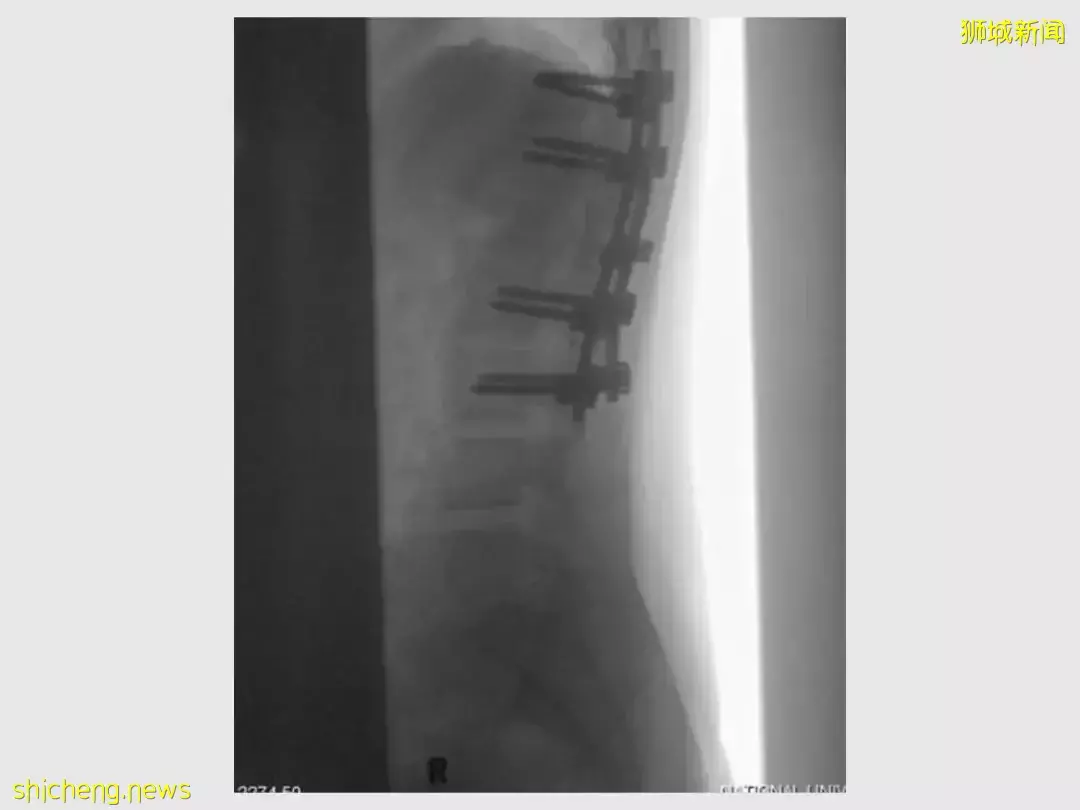

最后,她骨折和脱臼的脊柱使用八个螺钉和两根金属棒将其固定到位。还得知医生说她有很大可能无法再次行走。

后来,她花了将近一年的治疗和背部强化治疗才能够正常行走。